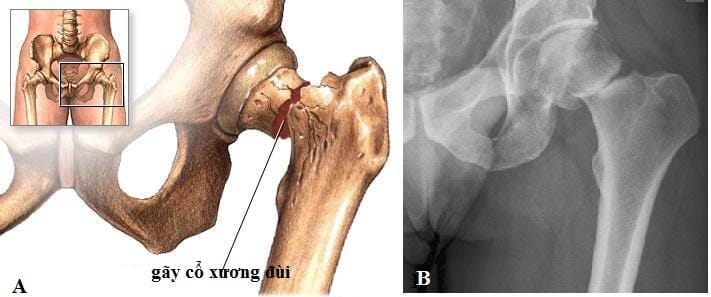

- Gãy cổ tay, gãy khớp háng, cong vẹo cột sống…